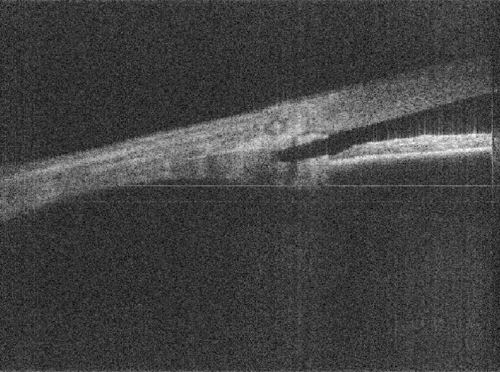

Duke University's FDOCT method reduces artefacts in the image and allows researchers to see deeper into the crucial drainage angle area of the eye's anterior chamber.

Image credit:

Sanjay Asrani, Duke University Medical Centre.